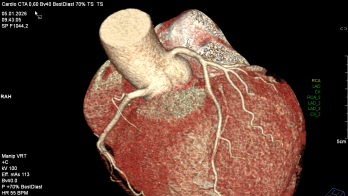

Kardiale Bildgebung

Jahrelang galt die Herzkatheteruntersuchung als das Nonplusultra zur Beurteilung der Herzkranzgefäße. Bezogen auf die Einwohner eines Landes ist Deutschland diesbezüglich Weltmeister. Und dennoch: Im Vergleich mit anderen westeuropäischen Ländern landet Deutschland bei der durchschnittlichen Lebenserwartung weit hinten. Der Grund: Im Kampf gegen Herz-Kreislauf-Erkrankungen, der häufigsten Todesursache, ist Deutschland deutlich weniger erfolgreich als andere Länder.

Es stellt sich also die Frage: Bekommen unsere Patienten die passende Diagnostik? Denn mittels geeigneter Diagnostik kann man die richtige Behandlung veranlassen. Viele Fragen lassen sich heute nicht-invasiv mittels kardialer Bildgebung (Kardio-CT & Kardio-MRT) beantworten und so eine individualisierte Therapie für unsere Patienten ableiten.

In Zusammenarbeit mit der Abteilung für Radiologie bieten wir ihnen das komplette Spektrum moderner kardialer Schnittbildgebung. Vereinbaren Sie einen Termin mit unseren Experten.